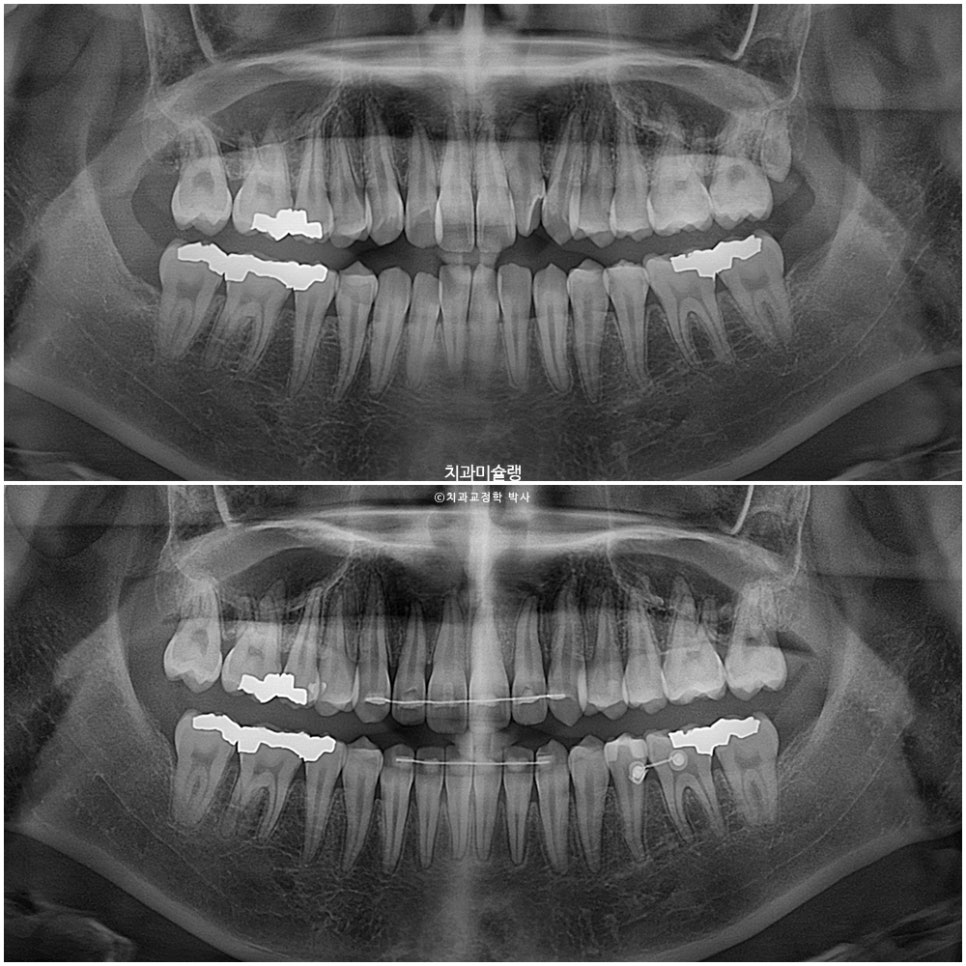

사랑니 공간으로 어금니들이 계획대로 2mm씩 후방이동 한것이 엑스레이로 확인됩니다.

교정치료 기간 동안 치근흡수는 없으며 치근 평행도는 좋습니다.

사랑니 공간으로 어금니들이 잘 이동 된것이 보입니다.

- Sequential posterior movement of molars by 2mm using mini-screw anchorage

- No root resorption observed with good root parallelism achieved